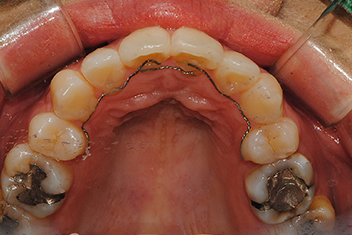

앞니 돌출 해소 케이스1

치료 기간16개월

심한 앞니 돌출을 투명교정으로 점진적으로 개선